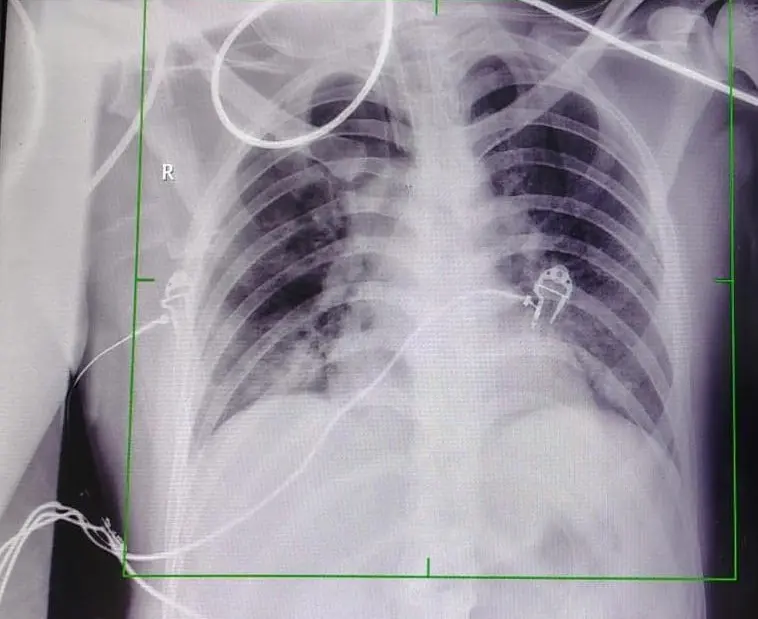

भोपाल। पत्थरों की चमक के पीछे हजारों मजदूरों की जिंदगी को निगलने वाली एक खामोश बीमारी सिलिकोसिस भी छुपी होती है। यह एक ऐसी बीमारी है, जिसका कोई स्थायी इलाज नहीं है। इसमें फेफड़े पत्थर जैसे सख्त हो जाते है और मरीजों को सांस लेना तक मुश्किल हो जाता है। ऐसा ही एक मरीज गंभीर हालत में AIIMS भोपाल पहुंचा। उसे सांस लेने में परेशानी हो रही थी। जांच के दौरान पता चला कि मरीज के दोनों फेफड़ों में एक खास तरह का प्रोटीन जमा था, जिससे फेफड़े भी सख्त हो गए थे। मरीज की स्थिति ऐसी थी कि अगल जल्द उपचार नहीं किया जाता तो उसकी मौत भी हो सकती थी। ऐसे में AIIMS में होल लंग्स लैवेज प्रक्रिया को अपनाकर सलाइन वाटर से फेफड़ों को धोकर प्रोटीन को साफ किया। AIIMS प्रबंधन की मानें तो मध्य भारत में पहला मौका है जब लंग्स पर जमे प्रोटीन को पानी से धोकर साफ किया हो।

इस पूरी प्रकिया को एम्स के पल्मोनोलॉजी विभाग के प्रो डॉ. अल्केश खुराना और असिस्टेंट प्रोफेसर डॉ. अभिनव खुराना द्वारा संपन्न किया गया। डॉ. खुराना के मुताबिक मरीज स्टोन क्रशर में काम करता था, जिससे वहां उड़ने वाली धूल उसके फेफड़ों में जम गई थी। इसे डिफ्यूज एल्जियोविर प्रोटिनोसिस भी कहते हैं। उन्होंने बताया कि इसके लिए एंजियोग्राफी के दौरान सलाइन वाटर से फेफड़े को साफ किया गया। यह प्रक्रिया बहुत जटिल होती है, क्योंकि फेफड़े में 6 से 8 लीटर पानी डालने से मरीज की मौत भी हो सकती है। इसलिए करीब 6 घंटे में पूरी प्रकिया हो सकी।

इस प्रोसीजर में कार्डियक थोरेसिक सर्जन डॉ. योगेश निवारिया भी शामिल थे। उन्होंने बताया कि यह प्रक्रिया इसलिए कठिन है क्योंकि एक फेफड़े को साफ करने के दौरान मरीज दूसरे फेफड़े पर ही निर्भर रहता है। इस मरीज का दूसरा फेफड़ा भी पूरी तरह से कमजोर था। ऐसे में मरीज को हार्ट लंग्स मशीन (आर्टिफिशियल लंग्स) पर रखना पड़ सकता है। हालांकि इस मरीज को इसकी जरूरत नहीं पड़ी।